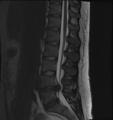

• Magnetic resonance imaging (MRI) without contrast is a diagnostic test that produces three-dimensional images of body structures using powerful magnets and computer technology. It can show the spinal cord, nerve roots, and surrounding areas, as well as enlargement, degeneration, and tumors. It shows soft tissues better than CAT scans. An MRI performed with a high magnetic field strength usually provides the most conclusive evidence for diagnosis of a disc herniation. T2-weighted images allow for clear visualization of protruded disc material in the spinal canal.